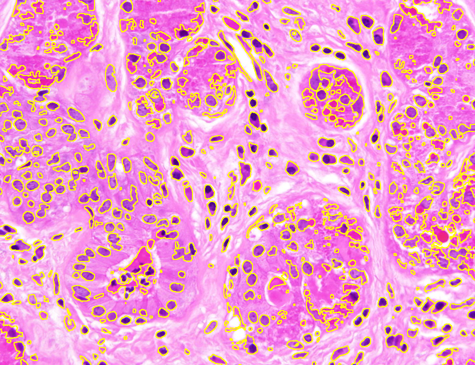

Dataset 3 consists of 50 annotated H&E-stained histological images from triple-negative breast cancer patients [74]. The images were acquired at 40× magnification using a Philips Ultra Fast Scanner (1.6RA) at the Curie Institute and contain a total of 4022 annotated cells.

Representative samples from the three datasets are shown in Fig. 1. In (a), the first frame of the synthetic video in Dataset 1 illustrates the strong illumination gradients produced by distance-dependent shading together with orientation-dependent interactions between vertex normals and the light direction. The H&E images in (b) and (c), also from Dataset 1, depict a mast cell infiltrate from a patient with non-alcoholic steatohepatitis and cirrhosis and, respectively, a sample from a patient with sclerosing polycystic adenosis of the parotid gland; the former consists primarily of purple nuclei, white cytoplasm, and pink extracellular tissue. Subfigures (d) and (e) show two examples from Dataset 2 accompanied by their ground-truth nuclei annotations, while (f) and (g) present a representative image from Dataset 3 together with its corresponding cell mask.

Figure 1: Samples from Datasets 1–3. (a) First frame of the 74-frame video in Dataset 1 (1770 × 880) with a superimposed red mesh. (b,c) H&E-stained tissue images from Dataset 1 (1000 × 750; 950 × 730). (d,e) Cell images from Dataset 2 (600 × 600) with nuclei annotations. (f,g) Image from Dataset 3 (512 × 512) with annotation.

On Dataset 3, the resulting DSC values, shown in Table 1, are lower than those for Dataset 2. This difference is mainly caused by the fact that Dataset 3 provides pixel-level annotations, whereas Dataset 2 only includes nuclei center annotations. The computation times for AR and ZZ are shorter due to the smaller image size (512×512512\times 512 vs. 600×600600\times 600 in Dataset 2). SP achieves a DSC improvement of 3.62 over SAM, despite being roughly twice as slow as SAM in the segmentation process. The results also show that SP achieves again the highest DSC performance (76.62), outperforming SMST (DSC 60.63), AR (DSC 61.35), and ZZ (DSC 65.33).